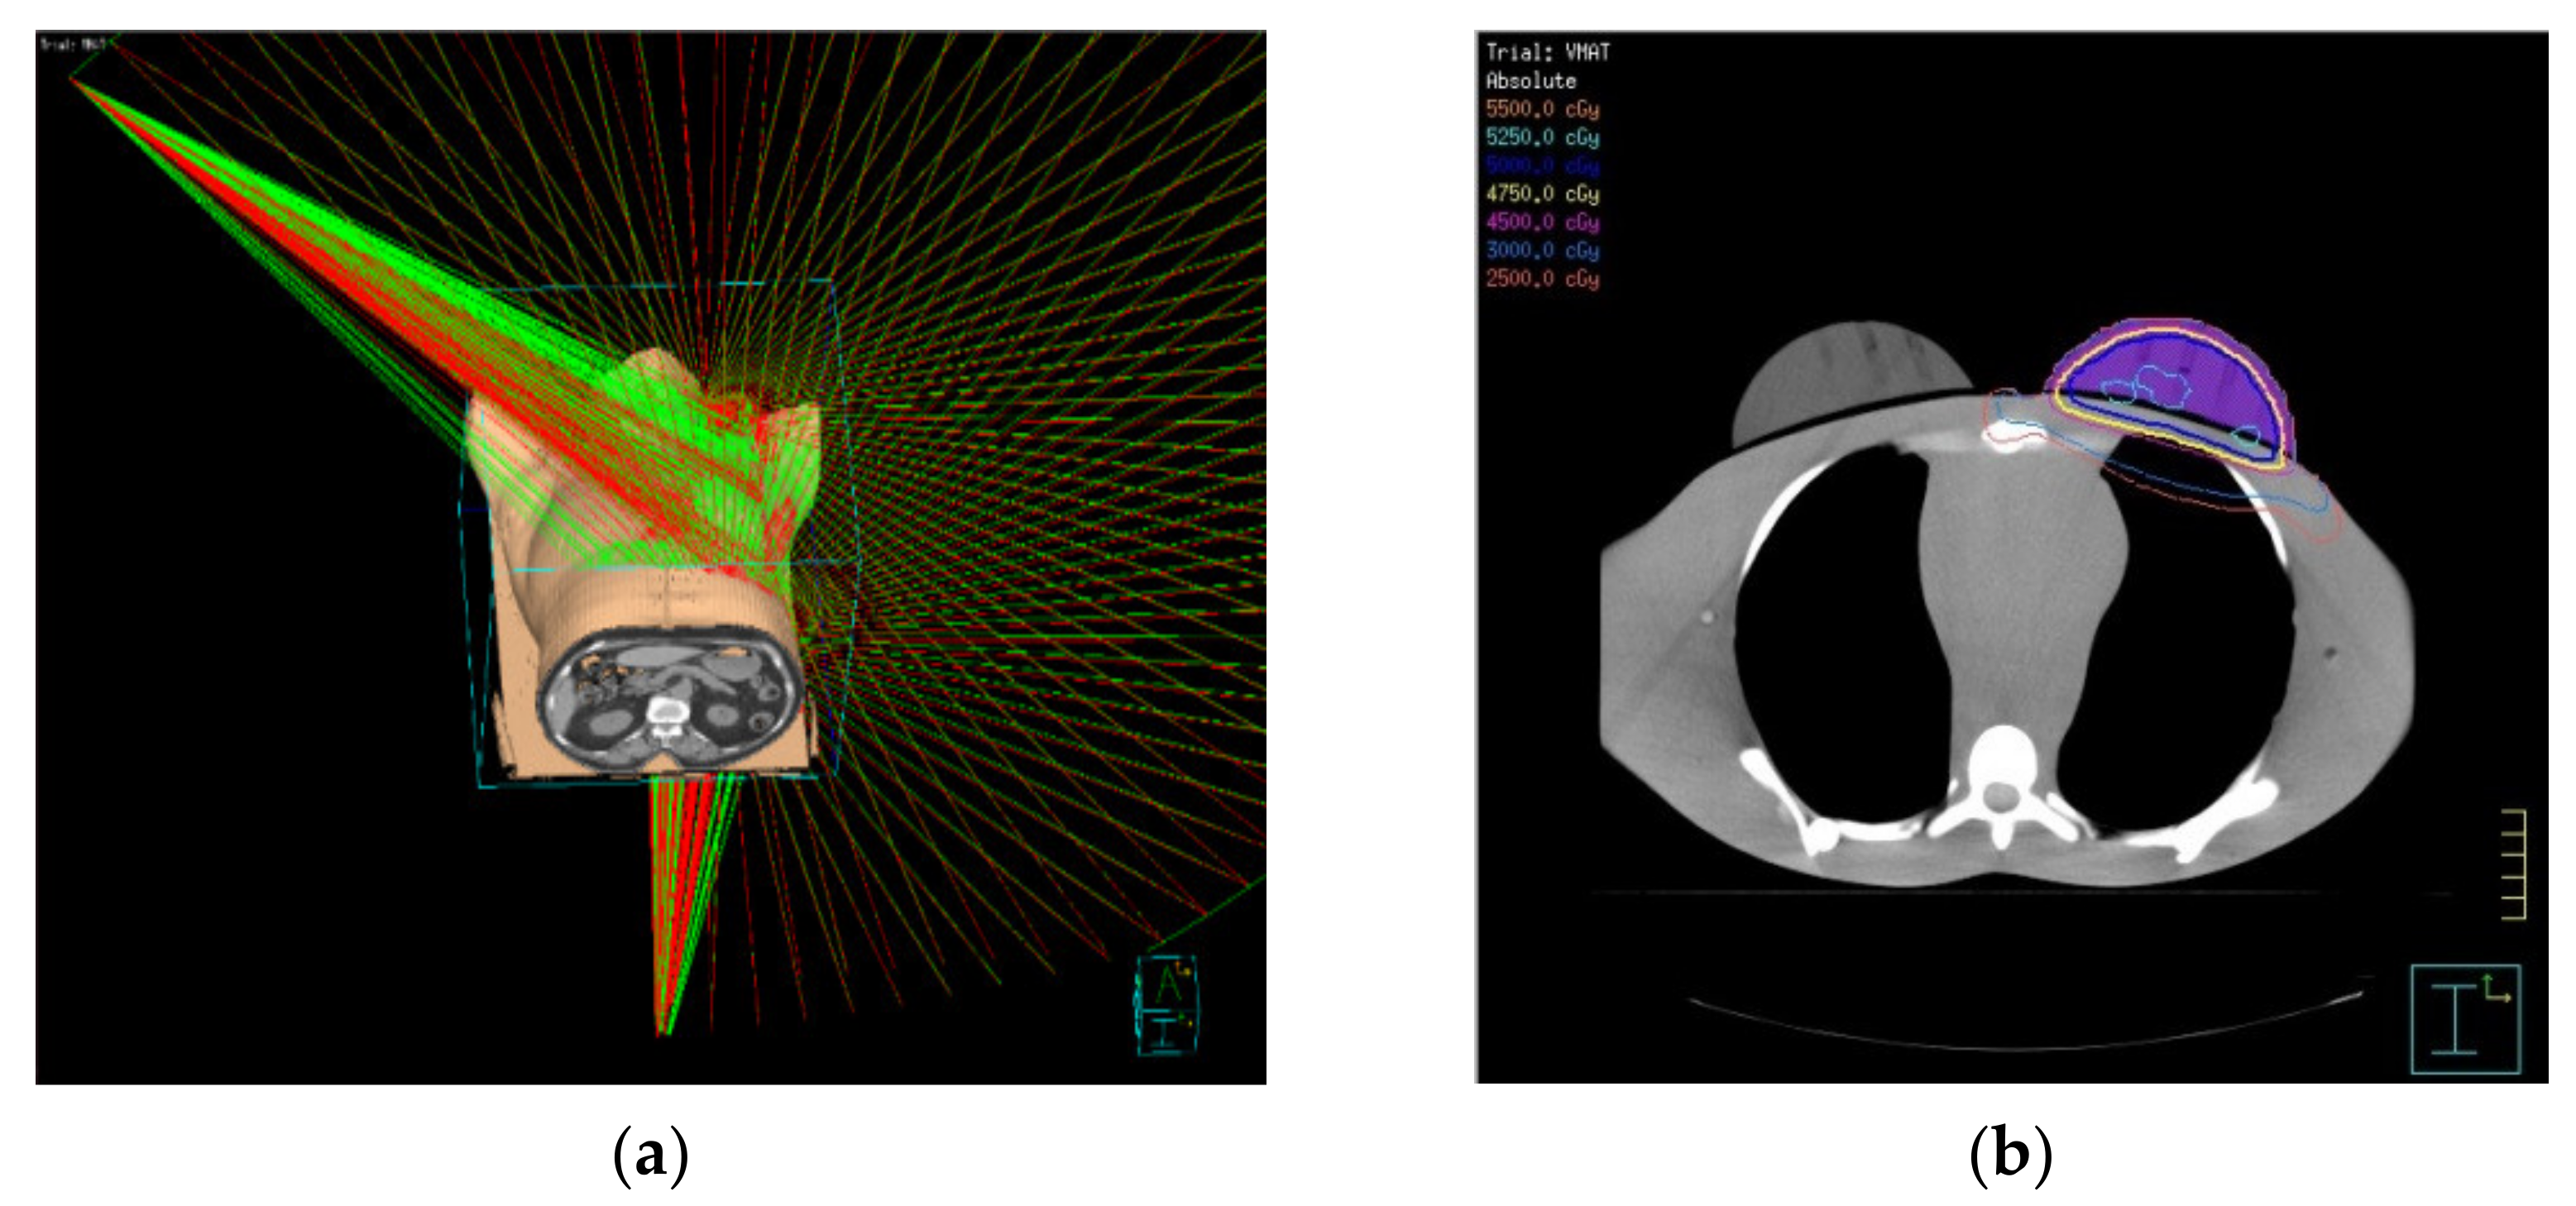

2.5. VMAT Treatment Planning